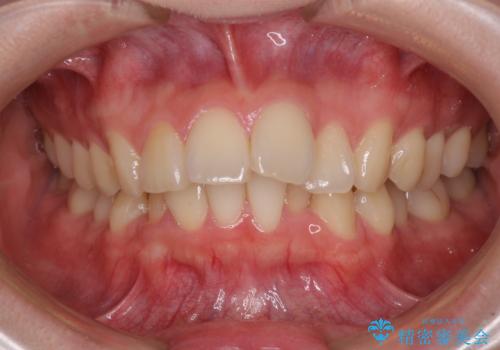

- 下顎の前歯が上顎の歯肉に咬みこむくらいに突出した上顎前歯を気にして来院された患者様です。

口元の突出感はないものの、上顎前歯が前方に傾斜して突出しており、前後に大きなズレがあり非常に深い咬み合わせとなっていました。